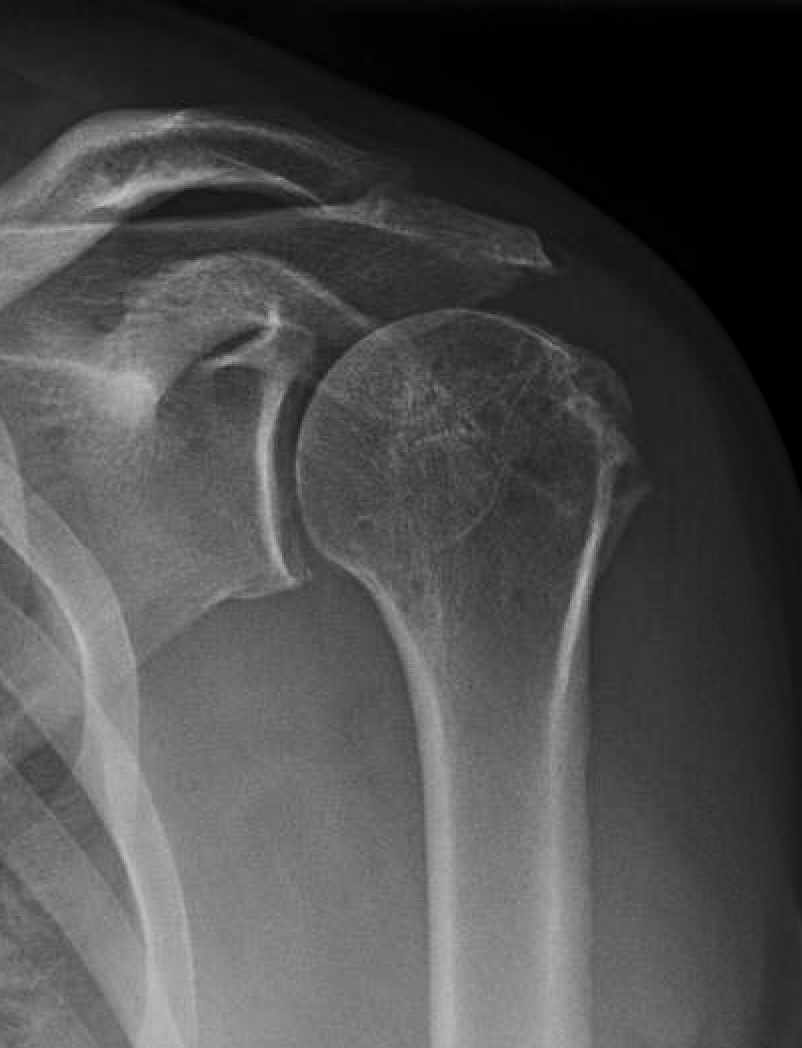

From stock.adobe.com

Rotator cuff SLAP tear torn pain injury tendon muscle joint Xray range Range Of Motion Rotator Cuff Tear Rotator cuff tears are a very common source of shoulder pain and decreased motion that can occur due to both traumatic injuries in young patients as well as. Before doing the following exercises, warm up. R o tat o r c u f f h o m e e x e r c i s e p r o g. Range Of Motion Rotator Cuff Tear.